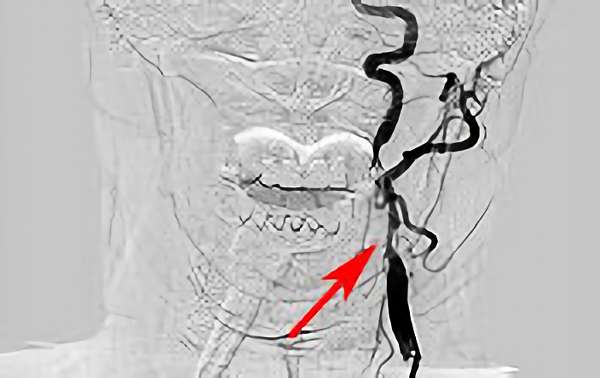

156

'18年6月16日

脳動静脈奇形

60代

院内外来

手術写真

治療

中

後

手術日